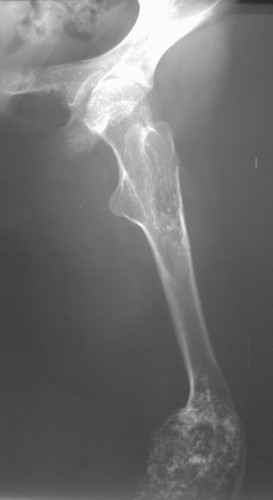

Диагноз: Дисхондроплазия. Варусная деформация дистального метафиза правой бедренной кости; состояние после оперативных вмешательств (1993 и 1994 гг.).

Деформация правой нижней конечности с 6 месяцев (стала прогрессировать после года, с момента начала ходьбы). Поставлен диагноз болезнь Олье, варусная деформация, укорочение правой нижней конечности на 4,5 см. 1993 г. - операция остеоклазия на уровне очагов поражения в н/3 правой бедренной кости и в/3 правой большеберцовой кости с одномоментной коррекцией деформации и фиксацией костных фрагментов спицами Киршнера. После начала статической нагрузки (1994 г.) появился рецидив деформации и укорочения. Вторая операция - ЧКО АВФ, аппарат демонтирован через 2 недели в связи с развившимся на уровне стержня переломом, после чего находилась в гипсовой повязке до консолидации костных фрагментов. Далее лечилась консервативно в гипсовой повязке. Выраженная деформация и укорочение правой нижней конечности. Относительная длина бедер: справа - 34 см, слева - 51 см; анатомическая длина голеней: справа - 29 см, слева - 39 см. Величина варусной деформации на уровне дистального отдела правого бедра составляет - 80 град. Амплитуда движений в коленных суставах (разгибание/сгибание ): справа - 0/0/100 град.; слева - 0/0/30 град. Отмечается боковая и ротационная нестабильность на уровне правого коленного сустава. Амплитуда движений в голеностопных суставах - в норме. Тактика лечения? Заранее благодарю! С уважением, А.В.Владзимирский